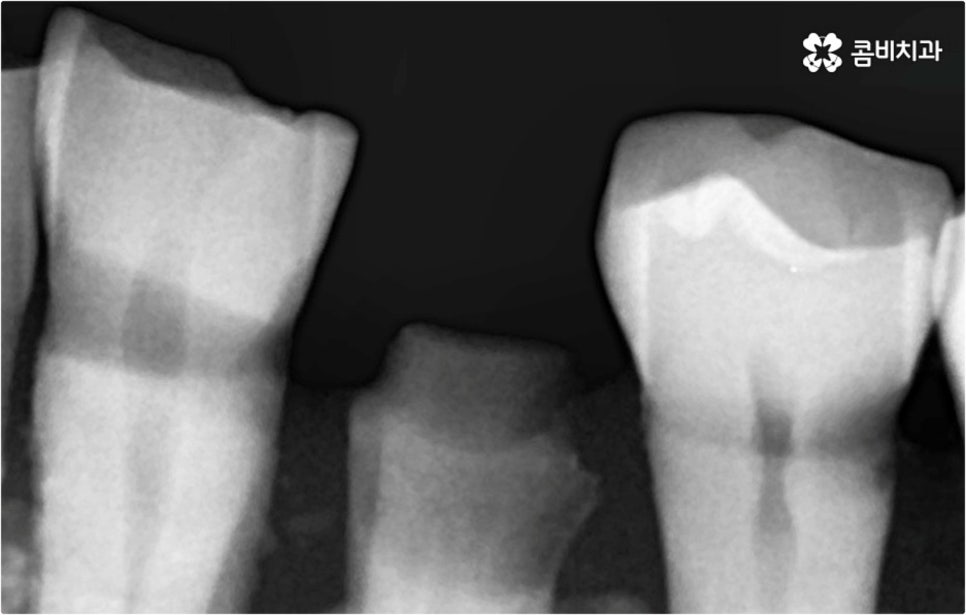

예를 들어 사고를 통해 한꺼번에 여러 개의 치아가 부러지거나 빠진 경우 연령 또는 전신 질환 여부 등을 살펴보고 치조골 상태가 양호하다면 보다 빠르고 간편한 당일 식립 방식을 이용해 볼 수 있어요. 그러나 하나 둘씩 치아가 빠질 때 마다 제때 치료를 해 주지 않아 치료 시기를 놓치고 결과적으로 무치악 상태에 이른지 오래 된 경우 또는 틀니를 오래 착용하여 잇몸뼈가 이미 많이 내려앉은 경우라면 바탕이 되는 잇몸뼈를 보충해 준 후 식립을 진행하는 방식을 이용해야 할 거예요.

또한 상악동과의 거리가 짧다면 거상술을 선행해야 할 수도 있고 심각한 치주 질환이 원인이라면 이를 먼저 깨끗하게 치료해 준 후 식립을 진행해야 성공률 또는 지속률이 높아질 수 있어요.